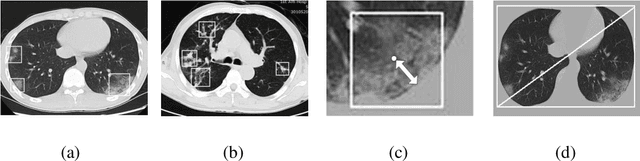

Abstract:We found that the real time reverse transcription-polymerase chain reaction (RT-PCR) detection of viral RNA from sputum or nasopharyngeal swab has a relatively low positive rate in the early stage to determine COVID-19 (named by the World Health Organization). The manifestations of computed tomography (CT) imaging of COVID-19 had their own characteristics, which are different from other types of viral pneumonia, such as Influenza-A viral pneumonia. Therefore, clinical doctors call for another early diagnostic criteria for this new type of pneumonia as soon as possible.This study aimed to establish an early screening model to distinguish COVID-19 pneumonia from Influenza-A viral pneumonia and healthy cases with pulmonary CT images using deep learning techniques. The candidate infection regions were first segmented out using a 3-dimensional deep learning model from pulmonary CT image set. These separated images were then categorized into COVID-19, Influenza-A viral pneumonia and irrelevant to infection groups, together with the corresponding confidence scores using a location-attention classification model. Finally the infection type and total confidence score of this CT case were calculated with Noisy-or Bayesian function.The experiments result of benchmark dataset showed that the overall accuracy was 86.7 % from the perspective of CT cases as a whole.The deep learning models established in this study were effective for the early screening of COVID-19 patients and demonstrated to be a promising supplementary diagnostic method for frontline clinical doctors.

Abstract:We developed a deep learning model-based system to automatically generate a quantitative Computed Tomography (CT) diagnostic report for Pulmonary Tuberculosis (PTB) cases.501 CT imaging datasets from 223 patients with active PTB were collected, and another 501 cases from a healthy population served as negative samples.2884 lesions of PTB were carefully labeled and classified manually by professional radiologists.Three state-of-the-art 3D convolution neural network (CNN) models were trained and evaluated in the inspection of PTB CT images. Transfer learning method was also utilized during this process. The best model was selected to annotate the spatial location of lesions and classify them into miliary, infiltrative, caseous, tuberculoma and cavitary types simultaneously.Then the Noisy-Or Bayesian function was used to generate an overall infection probability.Finally, a quantitative diagnostic report was exported.The results showed that the recall and precision rates, from the perspective of a single lesion region of PTB, were 85.9% and 89.2% respectively. The overall recall and precision rates,from the perspective of one PTB case, were 98.7% and 93.7%, respectively. Moreover, the precision rate of the PTB lesion type classification was 90.9%.The new method might serve as an effective reference for decision making by clinical doctors.